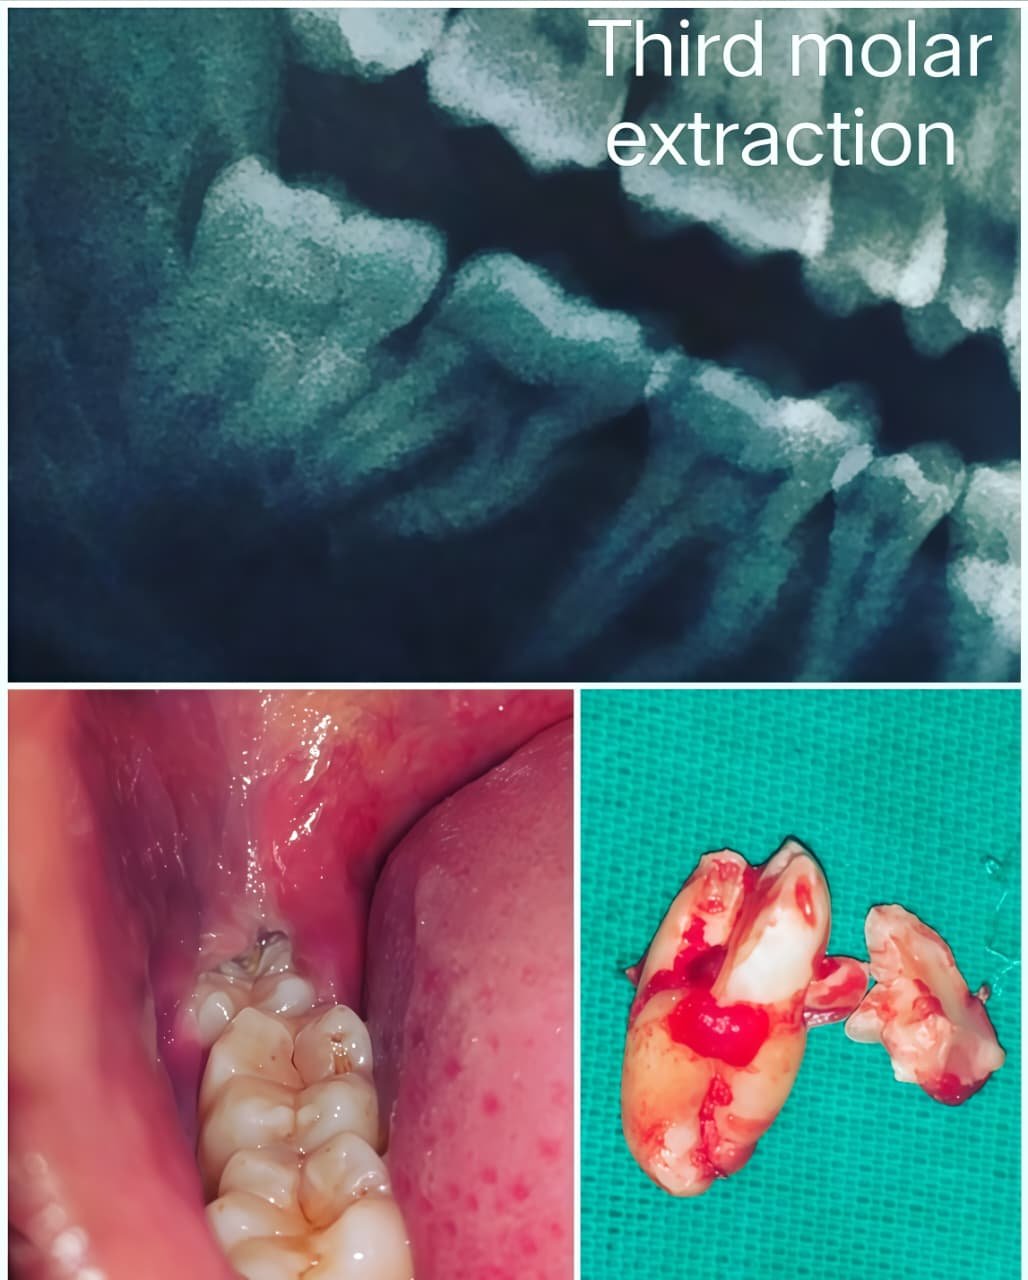

Before & After Case Studies

Our patients experience life-changing transformations. These cases demonstrate our commitment to exceptional results. Each success story represents our dedication to precision and aesthetic excellence.